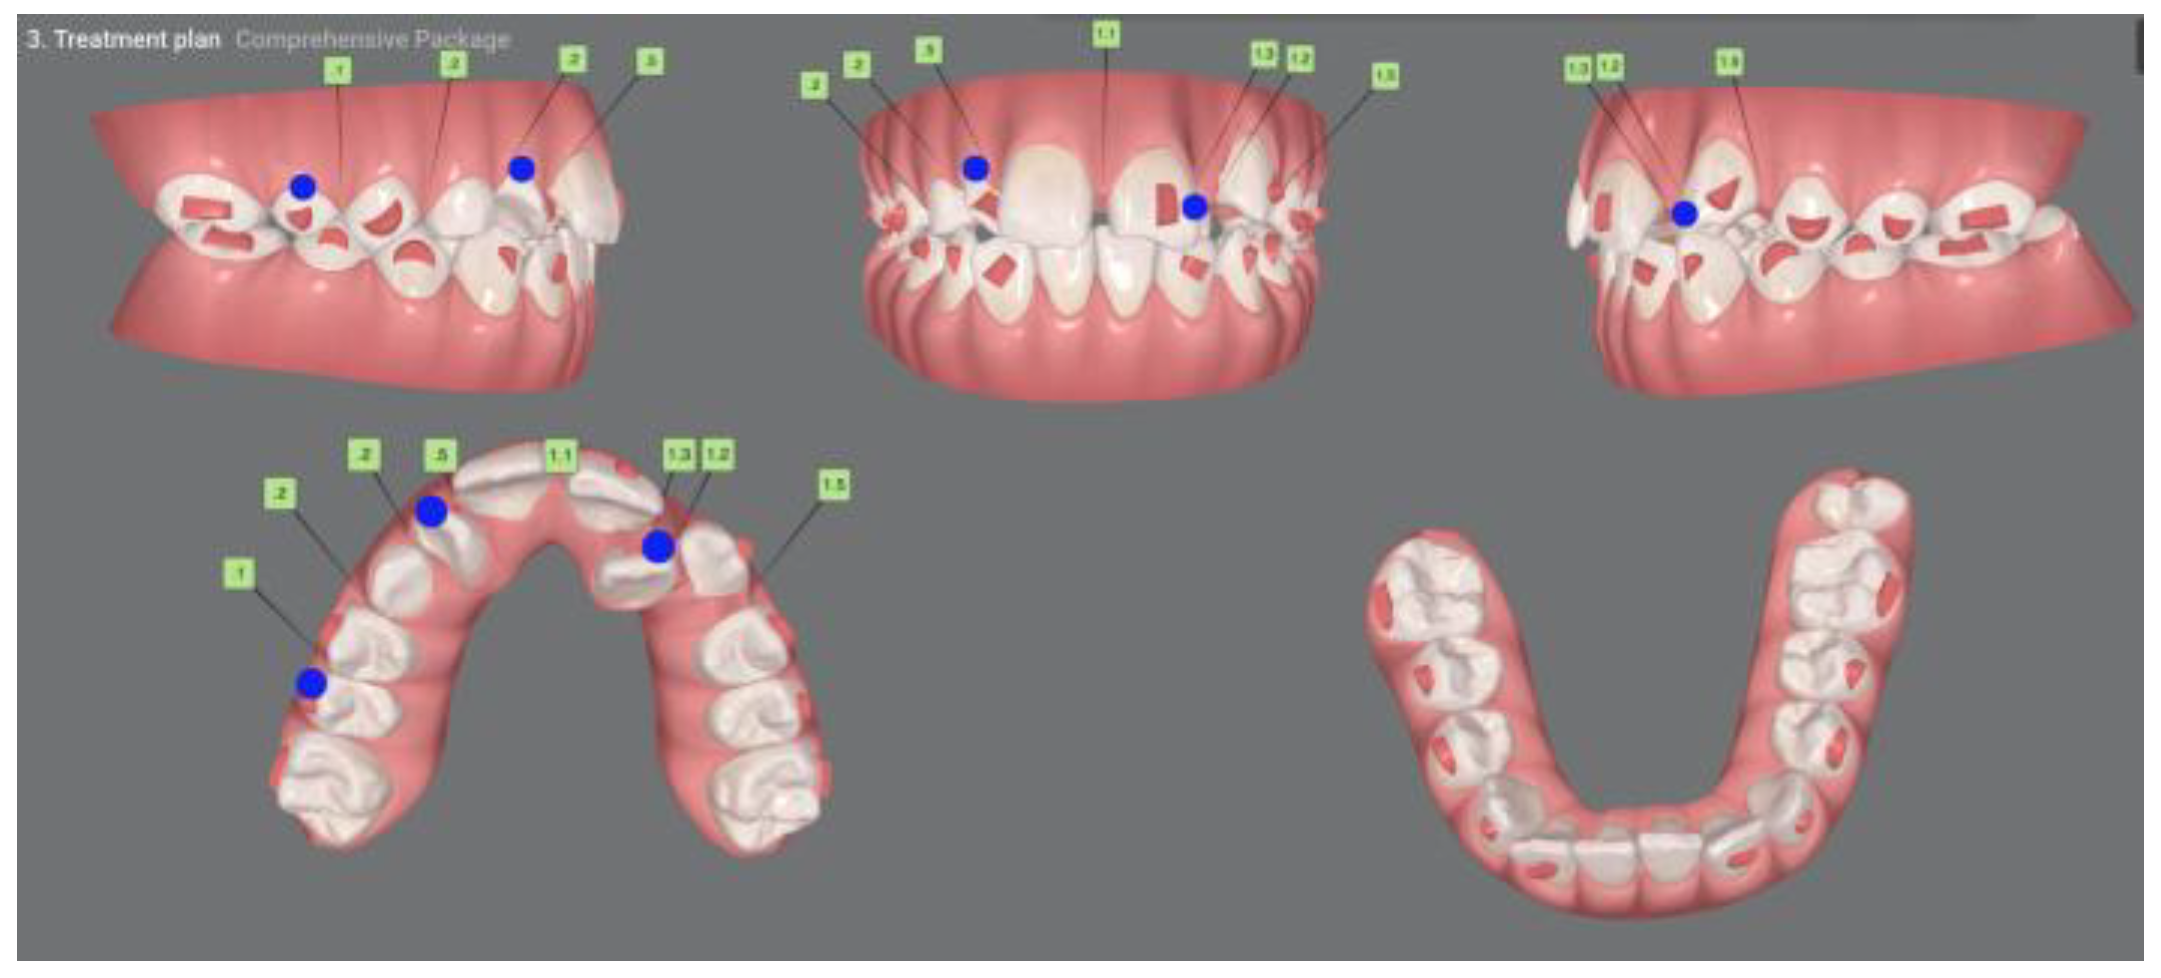

| Pinho T., Amaral R. 2025 | ♀ 13 YO | Mx.C.I1 | C | R | V (impacted) | Cl I | Maintained | -Total root resorption of tooth #11 due to the position of the ectopic canine |

3.2. Clinical Case